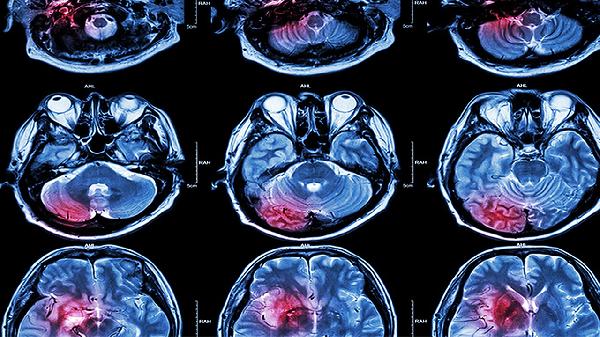

脑梗死脑梗塞脑栓塞有什么区别

脑梗死、脑梗塞、脑栓塞的区别主要在于发病机制和病因,治疗方法需根据具体情况采取个性化方案。脑梗死是脑部血液供应中断导致脑组织坏死,脑梗塞是脑血管阻塞所致,脑栓塞是栓子阻塞血管。治疗包括药物治疗、手术治疗和康复治疗,具体方案需根据病情选择。

1、脑梗死是由于脑部血液供应中断,导致脑组织缺血、缺氧而坏死。病因包括动脉粥样硬化、高血压、糖尿病等,治疗以改善脑血流、保护脑细胞为主,常用药物有阿司匹林、氯吡格雷、依达拉奉,必要时可进行血管内介入治疗或开颅减压术。

2、脑梗塞是由脑血管阻塞引起,常见于动脉粥样硬化斑块脱落或血管狭窄。治疗以溶栓、抗凝为主,常用药物有阿替普酶、肝素、华法林,严重者需进行颈动脉内膜剥脱术或血管成形术。

3、脑栓塞是栓子从其他部位脱落并随血流阻塞脑部血管,常见于心房颤动、心脏瓣膜病等。治疗以抗凝、溶栓为主,常用药物有华法林、利伐沙班、阿替普酶,必要时可进行左心耳封堵术或血栓切除术。